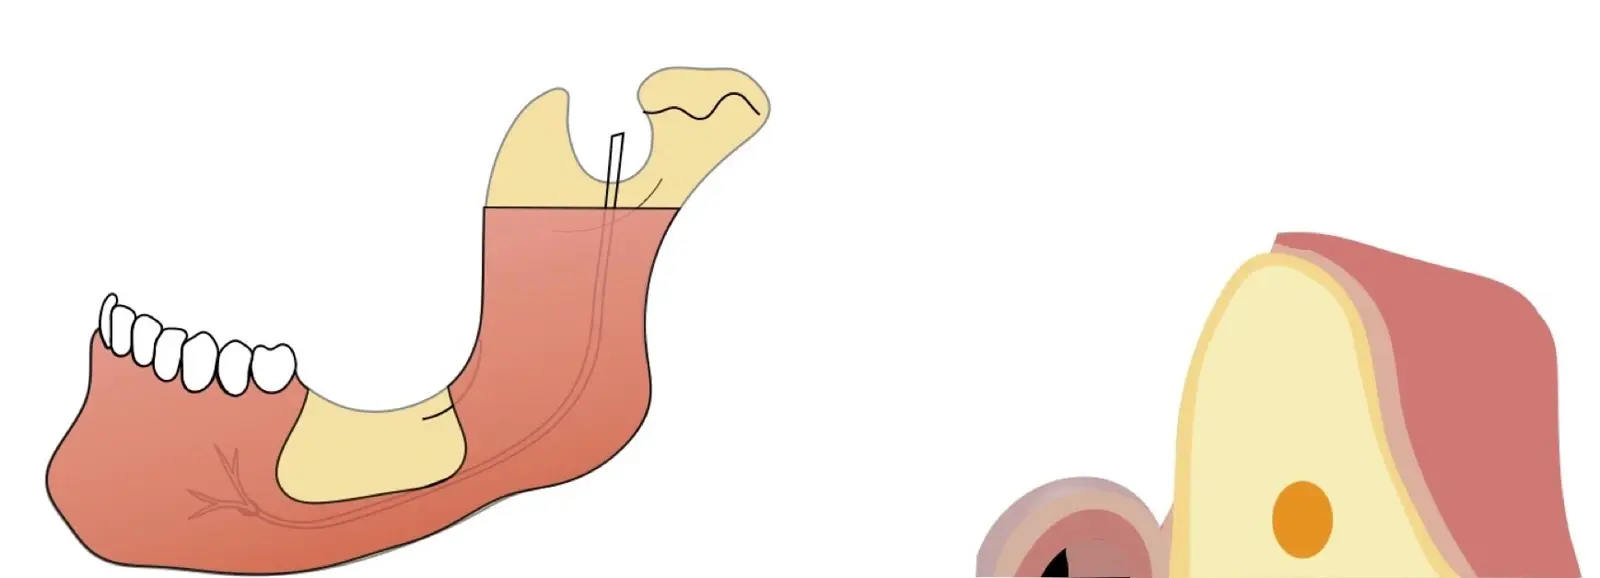

Figura 3. Imagen comparativa de corte con piezoeléctrico y trefinas. Foto: cortesía Dr. Claudio Nóia.